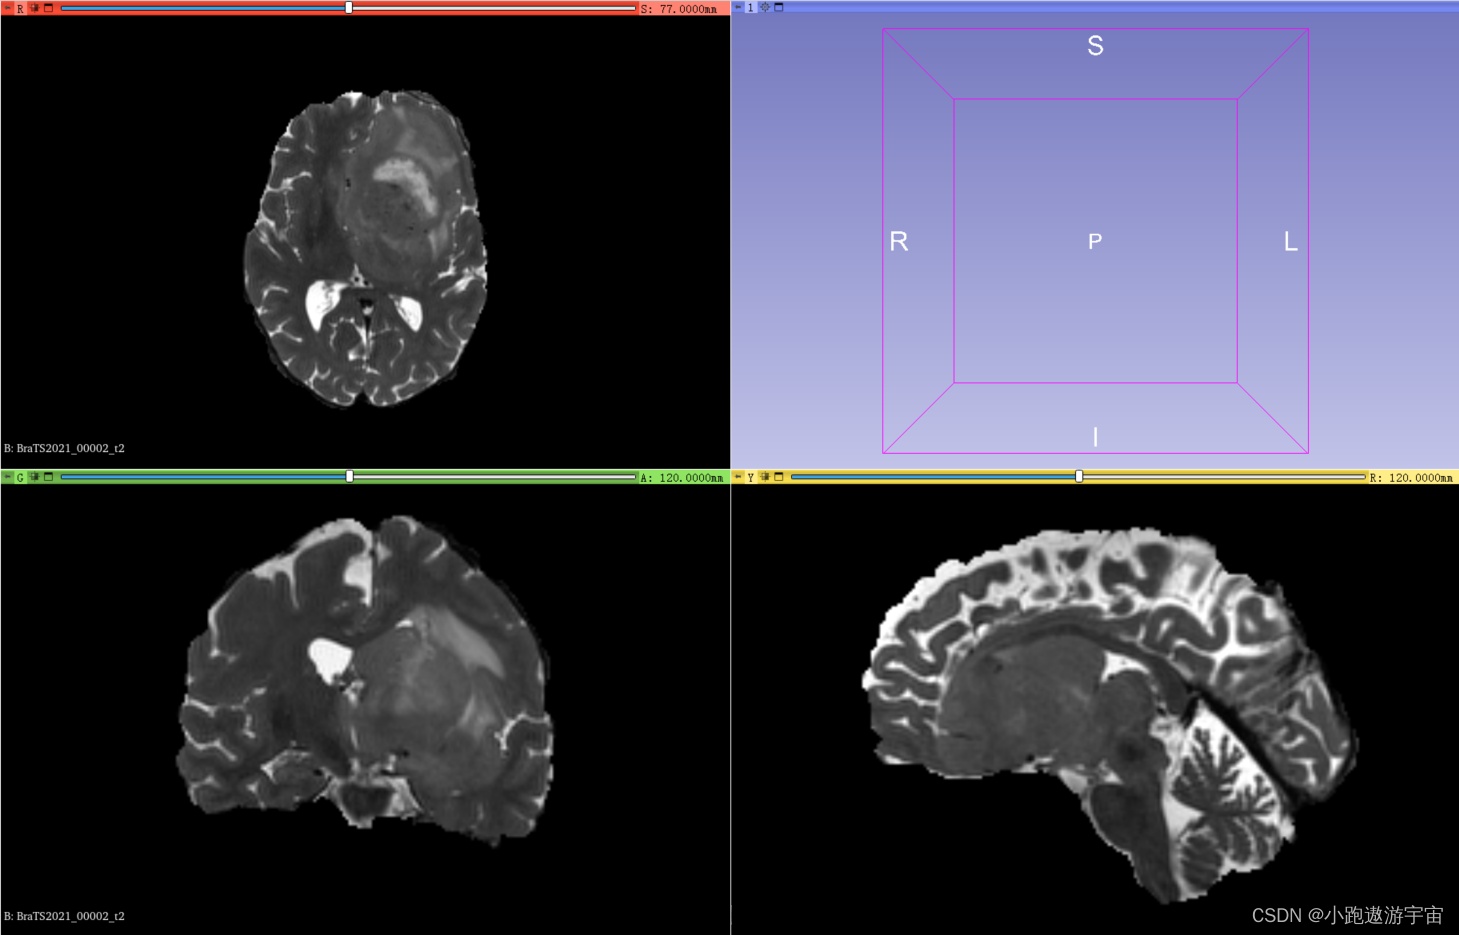

训练集其中一例MRI扫描(包含4个模态的3D图像以及1个共享标签)

1、在训练集中包含1251例核磁共振成像扫描,每例扫描包含4种模态的3D图像以及1个共享标签,其中4种模态分别是t1、t1ce、t2、flair:

T2加权成像(T2-weighted imaging, T2 ):这种成像方式通过对人体进行磁共振成像,使用对T2信号敏感的成像方法,呈现出人体组织的水分布情况。T2序列主要用于显示病变的水肿或液体。

BraTS2021_00002_t2.nii.gz |

4、可视化使用3D Slicer查看图像和标签,可以直观的了解自己要用的数据集。左上角代表在Axial(轴向)视角下,可以查看由上到下的脑部二维切片;左下角代表在Coronal(冠状)视角下,可以查看由前到后的脑部二维切片;右下角代表在Sagittal(矢状)视角下,可以查看由左到右的脑部二维切片。